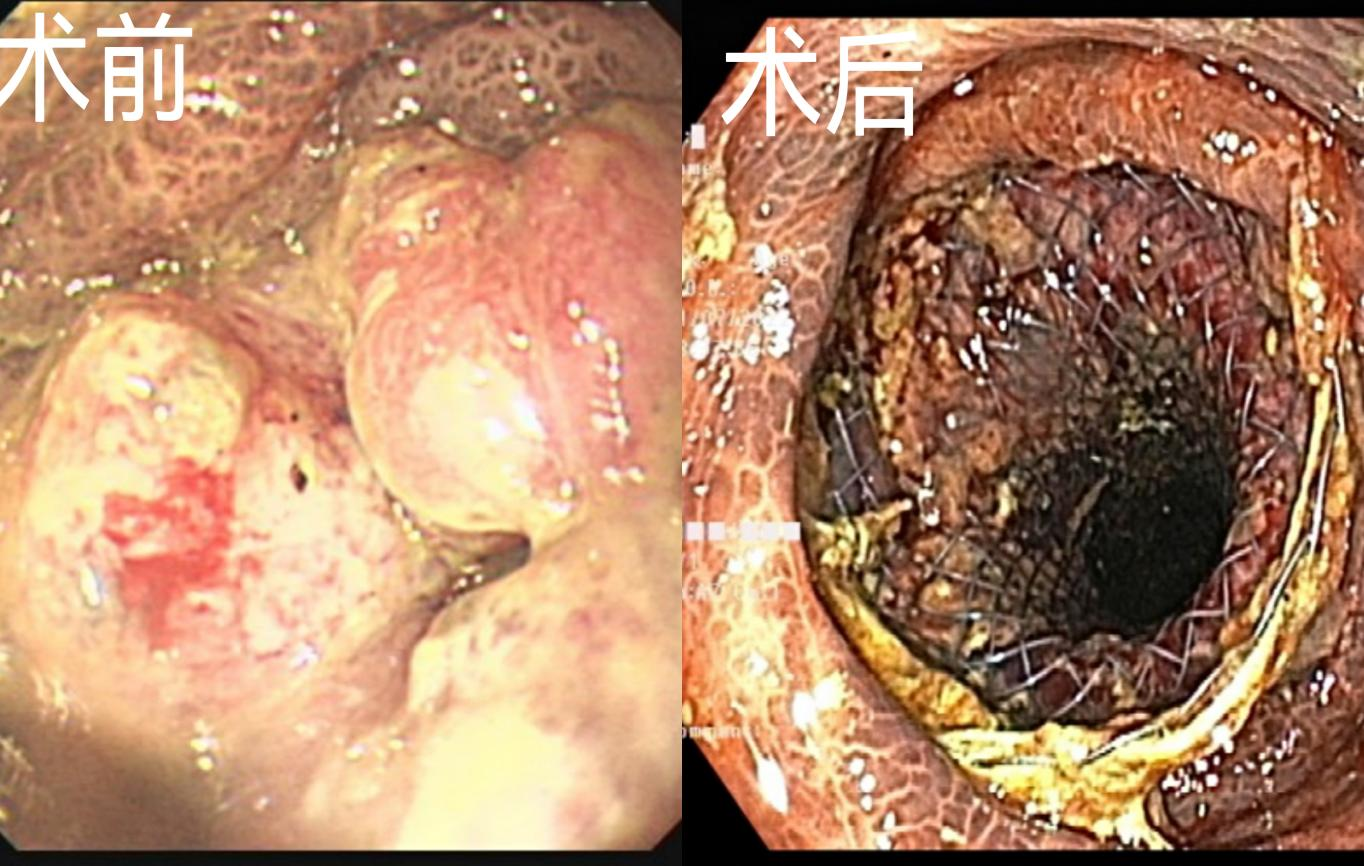

在清洁灌肠后为患者进行普通肠镜检查,发现管腔狭窄,再次与患者家属沟通后为患者行直肠支架置入术,支架释放后见大量粪便排出,手术顺利,患者术中及术后平稳,送回内二科接受下一步治疗。